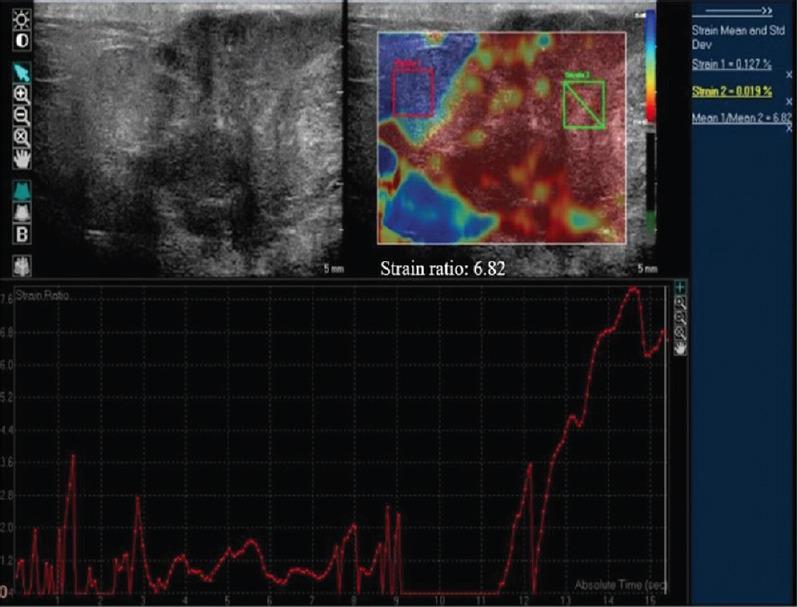

BACKGROUND & OBJECTIVES: : Ultrasound BI-RADS categories 3 and 4 constitute those breast masses which cannot be confidently classified as benign or malignant, owing to their morphological characteristics. These masses are further managed by follow up and biopsy, respectively. This study aims to evaluate the role of strain elastography and Doppler in better characterization of these sonographically indeterminate breast masses as benign or malignant.

: Fifty female patients with ultrasound BI-RADS 3 or 4 were evaluated with strain elastography and color Doppler including spectral analysis. Eight variables were assessed by elastography and Doppler, including a new phenomenon called bidirectional arterial flow (BAF). The findings were correlated with the gold standard diagnostic method of histopathology/cytology. Based on findings of combined elastography and Doppler method, the initial ultrasound BI-RADS categories of masses were re-categorized by up-gradation or down-gradation. Sensitivity, specificity, accuracy, positive predictive value, negative predictive value and receiver operating characteristic (ROC) curves were used to estimate the diagnostic performance of the combination method.

: Using ROC analysis, the positivity of ≥3 among the total eight variables correlated with malignancy on histopathology. Sensitivity, specificity and accuracy of the combination method using cut-off score ≥3 (i.e. at least three out of the eight parameters in the combination method being positive) for the prediction of malignancy was 100, 76.47 and 92 per cent, respectively, with the area under curve being 0.967. In addition, BAF was found predictive of malignancy with a diagnostic accuracy of 70 per cent.